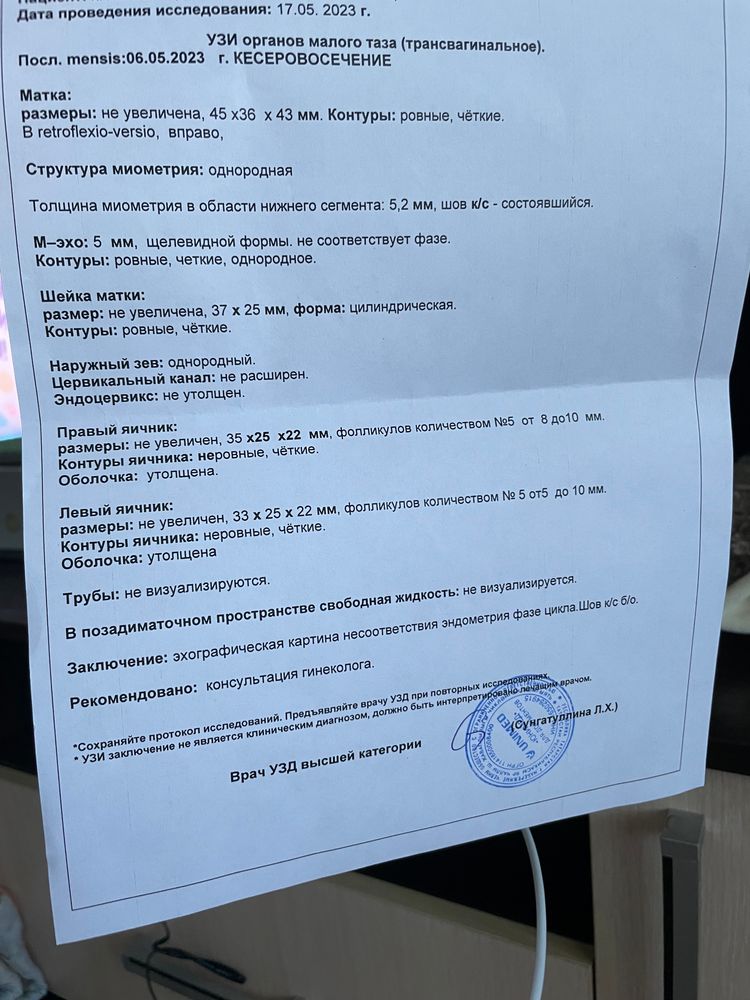

Узи матки !

Ходила на узи , проверяться и чисто узнать могу ли забеременеть за вторым . Вот что вышло результат. Это что значит ? Овуляции нет? Шов выдержит при беременности ? Родила первого 26.03.21 г, и потом операция еще была по шву кс резали 😟в октябре 2022года ( лопнул правый яичник) . Месячные были 6 мая до 12 мая .

Пока видно что овуляции нет , в связи с этим маленький эндометрий. Возможно у вас длинный цикл и еще рано. Напрягает утолщенная оболочка яичников, фолликулы могут не выйти.

Выглядит так , как будто у вас длинные циклы и еще не нарос эндометрий. нет доминантного фолликула . А сколько у вас цикл ?